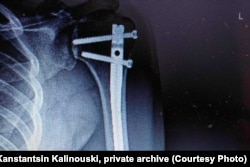

У Канстанціна быў пералом левай рукі, пералом крыжа і аскепкавы пералом у костцы патыліцы. Яго адразу адвезьлі ў шпіталь, працягвае аповед хлопец.

«Яны сьпехам зрабілі мне апэрацыю. Паставілі палку мэталічную мне ў руку», — кажа суразмоўца.

Здымак зламанай рукі Канстанціна Каліноўскага. Фота з прыватнага архіву